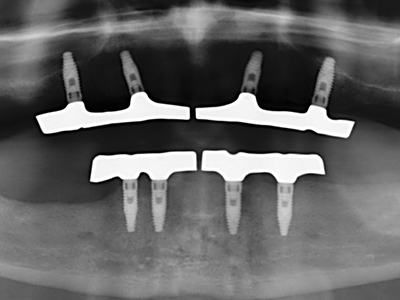

Piezosurgery has additional advantages when harvesting bone blocks. In addition to the high precision with osteotomy described above, the use of the thin saw tips specifically minimizes loss of material. Greater loss of material during harvesting can be expected with the thicker instrument tips, particularly when using Lindemann drills (Lakshmiganthan, Gokulanathan et al. 2012). The basal separation, which is necessary particularly for retromolar block transplants, is simplified by specially designed rectangular saws, with the result that piezosurgery is viewed as a precise, simple and safe procedure for harvesting retromolar bone blocks (Happe 2007) (Fig. 1-12).

Indication: Bone splitting

Bone tissue is not simply a mineral structure but also contains a substantial proportion of collagen fibres. This means it not only has good compressive strength but also a degree of flexibility, which can be taken advantage of when performing bone augmentations. In the classical expansion procedure using bone splitting, the atrophied alveolar ridge is split longitudinally and carefully expanded after reaching an adequate osteotomy depth (Fig. 13-16), ideally without substantial removal of the periosteum (Brugnami, Caiazzo et al. 2014, Stricker, Fleiner et al. 2014). Screw and plate systems with increasing expansion distance have proven effective in separating the two bone lamellae while remaining below the fracture threshold. In general, residual bone widths of at least 3–4 mm are required (Chiapasco, Zaniboni et al. 2006) to guarantee adequate flexibility and sufficient bone coverage of the future implants. If necessary, a vertical relief osteotomy on one or both sides can improve flexibility. A combination with additional augmentation techniques, particularly on the buccal side, has been described as an alternative to the classical technique.

The splitting procedure is particularly atraumatic and there is no significant loss of dimension when using piezosaws, and there are no significant differences between implants in split jaws and implants in an alveolar ridge without a bone deficit (Chiapasco, Zaniboni et al. 2006, Danza, Guidi et al. 2009). However, sufficient continuous irrigation is essential, particularly with locally restricted and deep splitting to prevent thermal stress in the apical osteotomy regions.